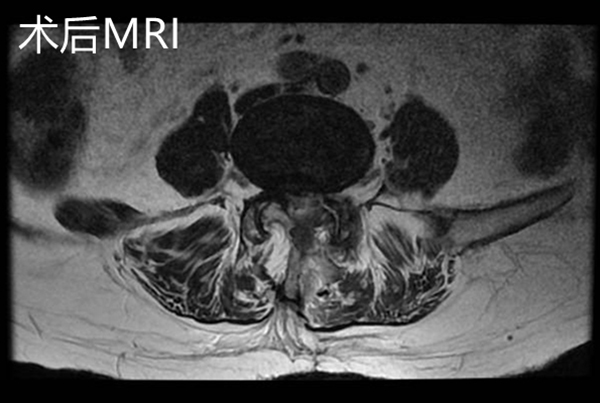

手術(shù)后復(fù)查腰椎MRI顯示:相應(yīng)的椎管狹窄及神經(jīng)根壓迫已解除,手術(shù)后第2天邱奶奶便可下地行走,腰痛及左下肢疼痛緩解,復(fù)查腰椎磁共振見(jiàn)L4/5左側(cè)狹窄已完全解除。手術(shù)后第4天,患者順利出院,沒(méi)有出現(xiàn)任何手術(shù)并發(fā)癥。